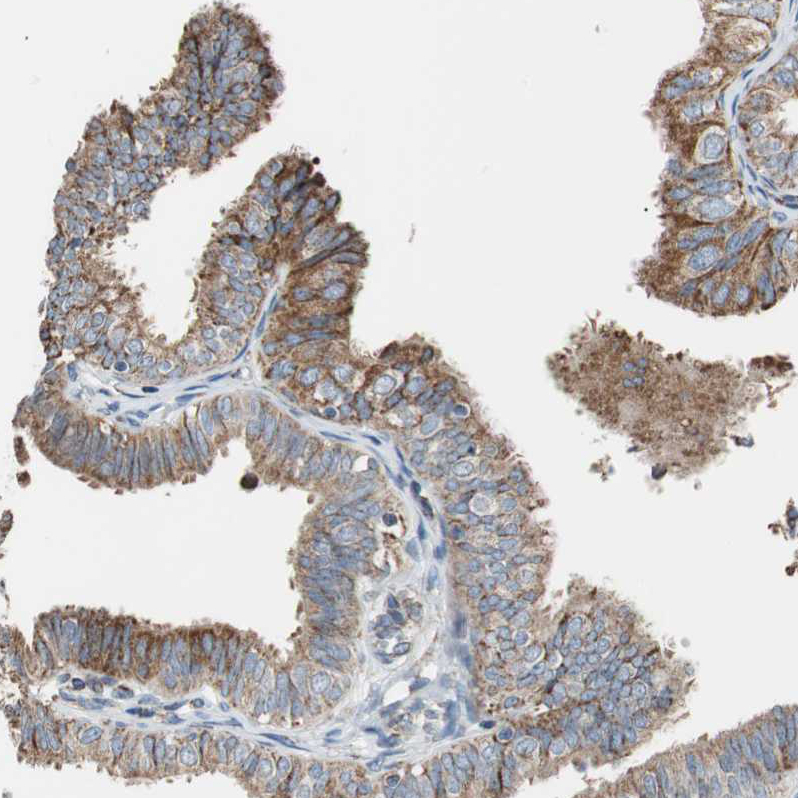

Immunohistochemical staining of human testis shows moderate granular cytoplasmic positivity in cells in seminiferous ducts and Leydig cells.